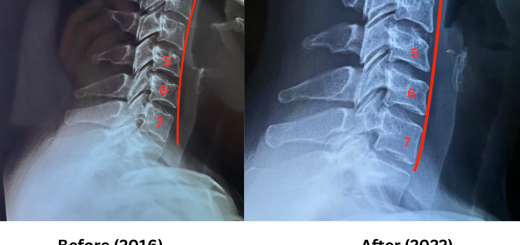

Degeneration of cervical spine

• Cervical Degeneration of the Neck causing Migraines and Numb Hands